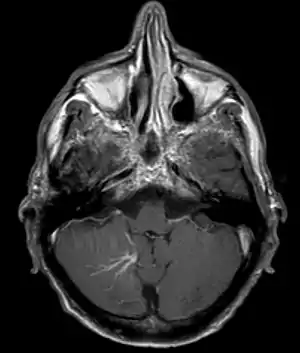

| Developmental venous anomaly in the cerebellum seen on axial contrast-enhanced T1 weighted MRI | |

DVA can be characterized by the caput medusae sign of veins, which drains into a larger vein. The drains will either drain into a dural venous sinus or into a deep ependymal vein. It appears to look like a palm tree.[1]